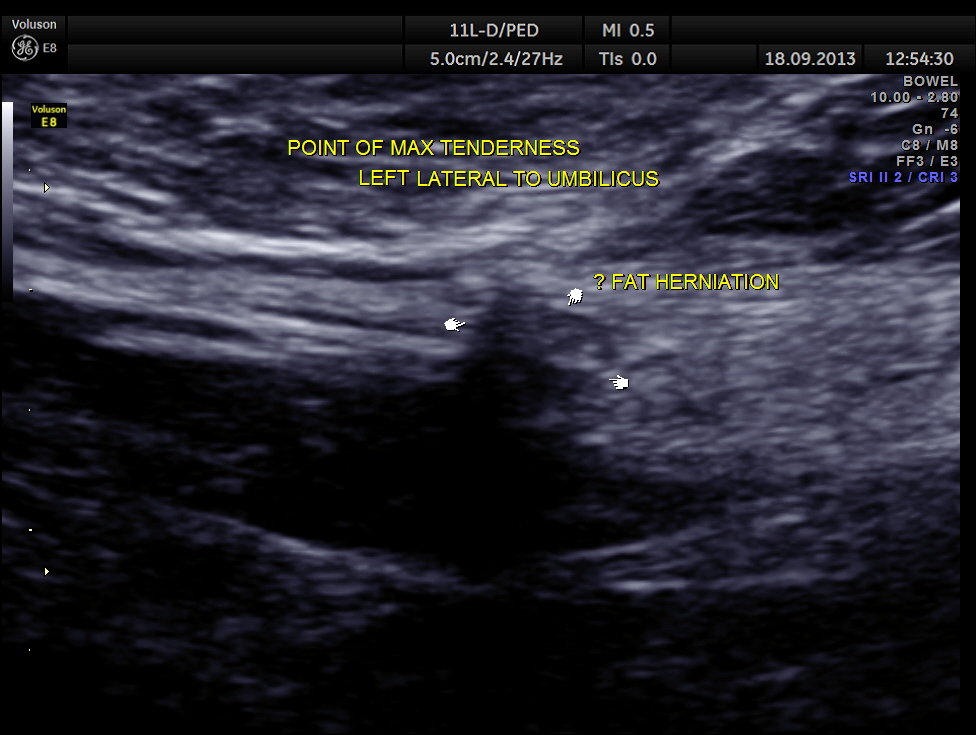

She came with history of localised pain to the left of the umbilicus for the past 18 days.

Scan with high resolution probe over the point of maximal tenderness revealed peritoneal fat herniation.

On specific questionig the patient said that 18 days ago she had to lift and move heavy objects in the house hold ( as her daughter was getting married ) !